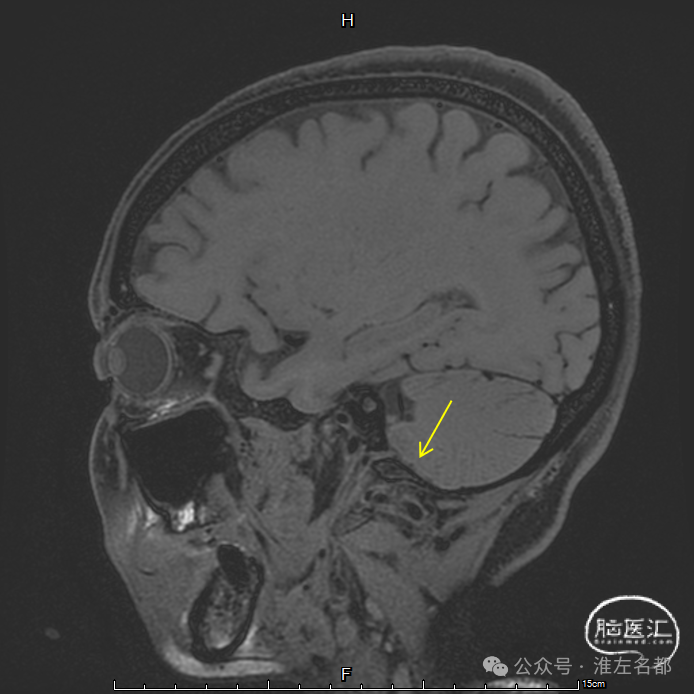

三维黑血高分辨T1平扫(上图)和增强(下图):左侧横窦发育细小。

三维黑血高分辨T1平扫(上图)和增强(下图):左侧乙状窦局部未发育。